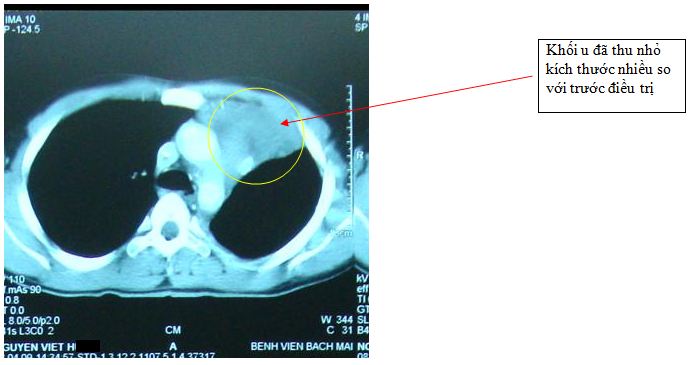

Chụp CT: + Trên hình ảnh chụp CT lồng ngực: Vùng trung thất có khối lớn xâm lấn toàn bộ khoang ngực trái gây xẹp phổi trái, tổn thương lan rộng ra vùng thành ngực

Trên phim chụp cắt lớp vi tính lồng ngực: Tổn thương u trung thất đã thu nhỏ kích thước hơn trước, phổi trái đỡ xẹp